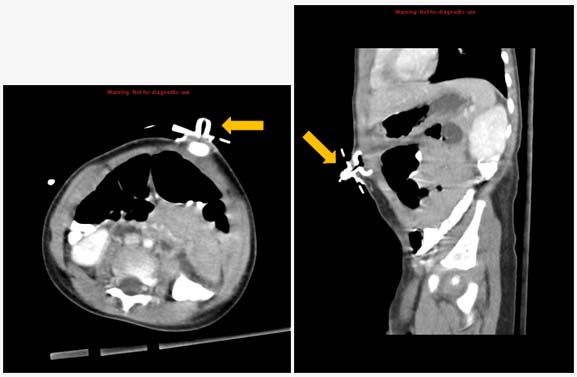

Figure 1. Abdominal CT shows internal bumper of the PEG tube within the abdominal wall (arrows).

Follow-up examination found a palpable, erythematous mass at the PEG tube site, presumed to be an abscess. A subsequent ultrasound study, however, was negative for abscess or fluid collection. Fluoroscopy with contrast found normal flow into the stomach. A CT scan of the abdomen showed that the internal bumper of the PEG tube had migrated and lodged between the abdominal wall and the skin (Figures 1 and 2), a phenomenon called buried bumper syndrome. The bumper was the palpable mass noted above. The PEG tube was removed by external traction and replaced with a Tri-Funnel tube without complications and the local infection resolved.